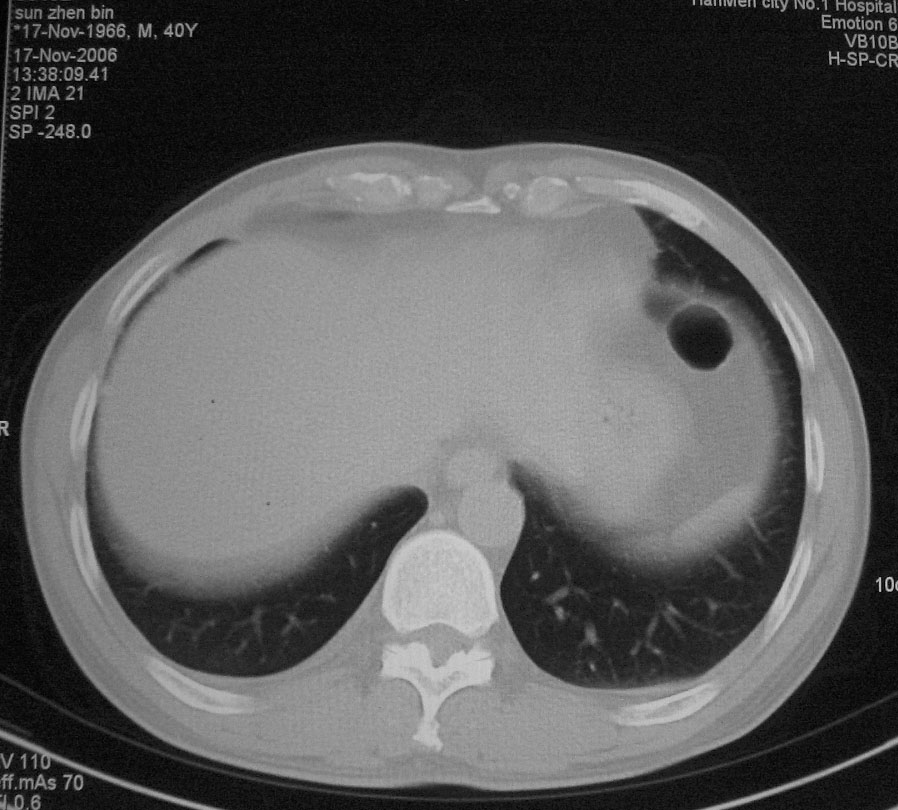

左肺上叶不张,左肺上叶支气管狭窄,呈鼠尾征,左侧胸腔内见少许积液,考虑左肺上叶中心型肺伴左侧胸腔内少许积液可能,不除外结核,建议支气管镜检查.

右肺上叶中央型肺癌并上叶肺不张、纵隔淋巴结肿大

右上叶支气管后壁明显增厚,支持右肺上叶中央型肺癌伴右上叶肺不张、纵隔淋巴结肿大。

左肺上叶不张,可见软组织肿块,左肺上叶支气管狭窄,呈鼠尾征,左侧胸腔内见少许积液,纵隔内未见肿大淋巴结,建义做个增强或支气管镜

右上叶支气管后壁明显增厚,支持右肺上叶中央型肺癌伴右上叶肺不张、纵隔淋巴结肿大。建议支气管镜检查。

右上叶支气管肺癌并右上叶阻塞性不张,右侧少量胸腔积液.

右上肺中央性肺癌伴右侧胸腔少量积液!右上肺胸膜下还有一小病灶,不完全排除结核,但个人支持恶性肿瘤!建议早穿刺活检。

右上叶支气管开口变窄,纵隔见肿大的淋巴结。支持右上叶中心型肺癌并右上叶不张纵隔淋巴结肿大。

右肺上叶中央型肺癌并上叶肺不张、纵隔淋巴结肿大.右侧少量胸腔积液。

右上肺中心型肺癌并肺不张,纵膈淋巴结肿大。右侧少量胸腔积液。